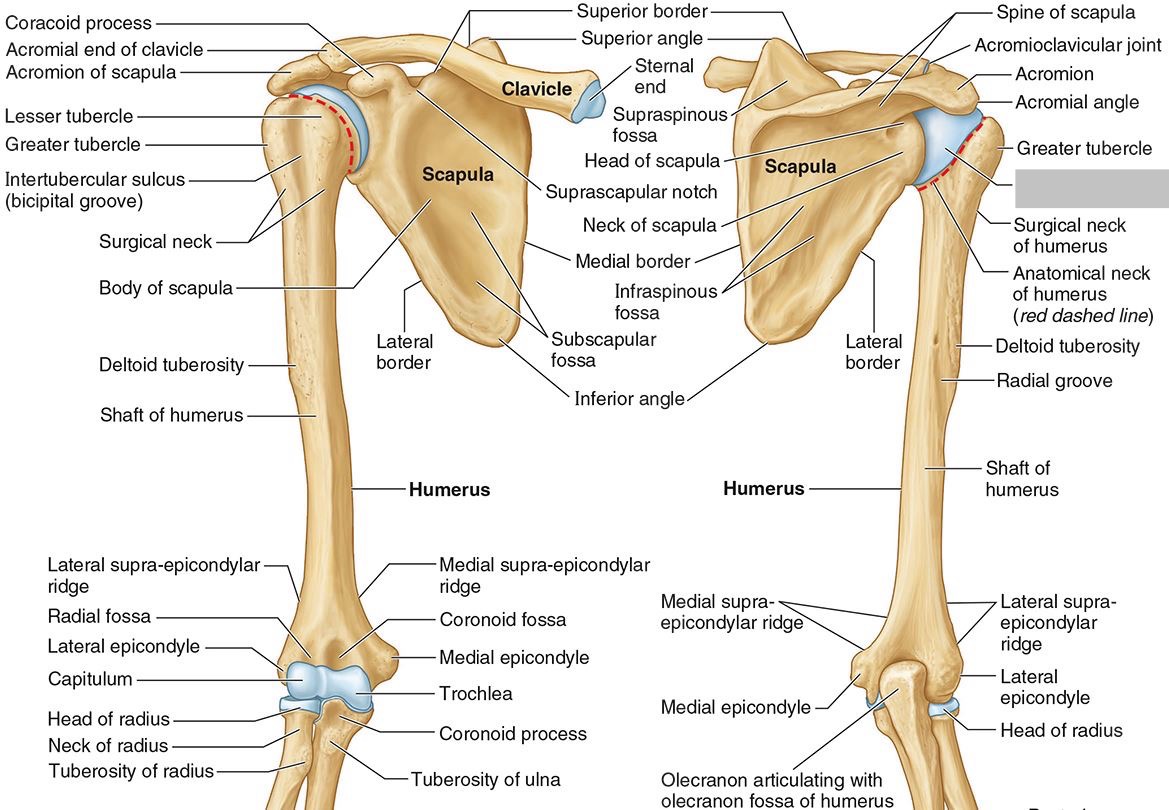

What is the only bone in the upper arm?

The humerus

What part of the humerus is this?

The head of the humerus articulates with the scapula at the glenohumeral joint.

What part of the humerus is this?

The anatomic neck is an indentation distal to the head and provides an attachment for the fibrous joint capsule of the glenohumeral joint.

What part of the humerus is this?

The greater tubercle lies lateral and distal to the anatomic neck.

What part of the humerus is this?

The lesser tubercle lies on the anterior/medial side of the humerus, just distal the anatomic neck.

What part of the humerus is this?

The intertubercular (bicipital) groove lies between the greater and lesser tubercles.

What part of the humerus is this?

The surgical neck is a narrow area distal to the tubercles. It is a common site for proximal humerus fractures.

What part of the humerus is this?

The humeral shaft features the deltoid tuberosity laterally for the distal insertion of the deltoid muscle.

What part of the humerus is this?

The radial groove is an oblique depression that contains the radial nerve and deep brachial artery.

Which parts of the humerus is this?

The medial and lateral epicondyles are distal prominences to which many forearm tendons attach, near the elbow joint.

Which parts of the humerus is this?

The medial and lateral supracondylar ridges extend superiorly from the medial and lateral epicondyles.

Which parts of the humerus is this?

The trochlea and the capitulum (the condyles) are the most distal surfaces of the humerus, where it articulates with the forearm bones at the elbow joint

What part of the humerus is this?

The olecranon fossa is a posterior depression above the trochlea that receives that olecranon process of the ulna

What part of the humerus is this?

The coronoid fossa is an anterior depression above the trochlea that receives that coronoid process of the ulna.